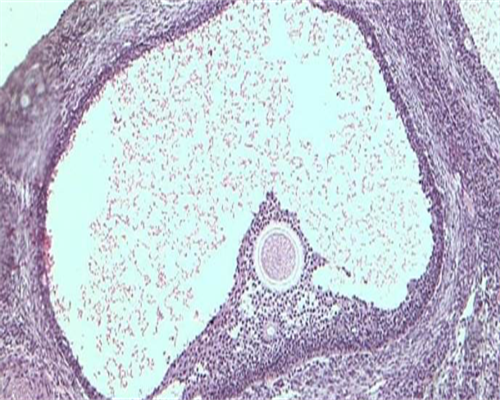

加纳医院妇科和生殖中心也不差,其生殖中心是云南省试管婴儿技术开展机构较早的医疗机构,去加纳医院做试管的姐妹还是很多的。

1、张晓梅,女,主任医师,从事辅助生殖技术近30年,擅长不孕不育诊治、女性生殖内分泌疾病诊治;

2、黄琴丽,女,副主任医师,一线工作25年,专注生殖医学及人类辅助生殖技术临床工作15年,擅长不孕不育症的诊断、促排卵方案的制定、药物选择、疑难病例及反复失败病例的个体化治疗。